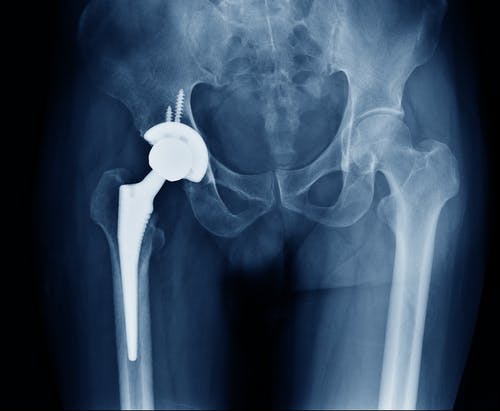

One medical device company that has been in the headlines for its substantial number of recalls is Exactech. Exactech is a global medical device company that is responsible for producing joint replacement devices. Within the past two years, the company has had to issue two recalls regarding knee, hip, and ankle replacements.

The first recall occurred in the summer of 2021 when a design defect was discovered in a hip liner model that is commonly attached to a hip replacement system. The defect led to a recall of nearly 90,000 hip replacement devices due to early device failure and premature wear. The second recall occurred in February of this year and occurred because there was a defect discovered in the knee replacement devices.

Patients with recalled Exactech devices may experience symptoms like swelling, instability in the affected joint area, bone loss, an inability to place weight on the affected area, and overall decreased mobility. When patients are experiencing these types of symptoms, healthcare providers may conduct an X-ray to study the status of the recalled device.

Depending on the results, the healthcare provider may recommend corrective surgery to remove the recalled device. For patients who do not experience these types of symptoms, corrective surgery may not be recommended. The decision to conduct corrective surgery will be determined by the healthcare provider and the patient.